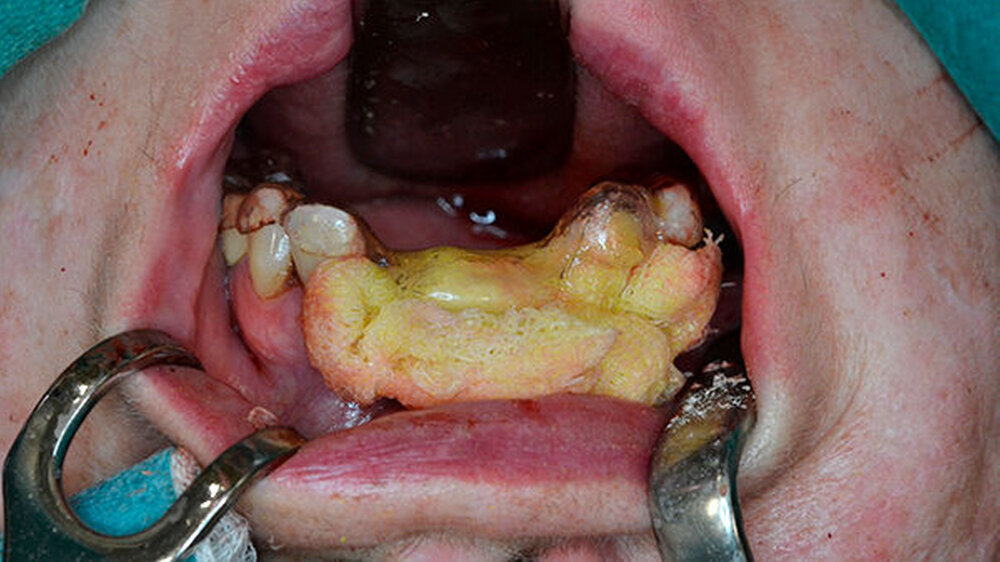

Nach erfolgter Tetrazyklinmarkierung mittels Doxycyclin 100 mg 1-0-0 für fünf Tage und präoperativer Abdrucknahme für eine Oberkieferverbandsplatte wurde der Eingriff in Intubationsnarkose durchgeführt. Nach marginaler Schnittführung wurden die Zähne 21, 12 und 13 entfernt sowie eine aufwendige modellierende Osteotomie im Sinne einer partiellen Resektion des Alveolarfortsatzes unter Schwartzlichtkontrolle in diesem Bereich durchgeführt (Abbildung 4).

Die Weichgewebsdeckung des entstandenen Defekts erfolgte mittels Mukoperiostlappen und einer Dreiecksaustauschplastik aus dem Oberkiefervestibulum (Abbildung 5). Nach spannungsfreiem, speicheldichtem Wundverschluss wurde eine Verbandsplatte mittels Jodoformvaseline durch eine Schraube am Gaumen knöchern fixiert (Abbildung 6). Daran schloss sich ein fünftägiger stationärer Aufenthalt unter strikter Ernährung mittels Magensonde sowie breiter intravenöser antibiotischer Abdeckung durch Clindamycin 600mg 1-1-1 an.